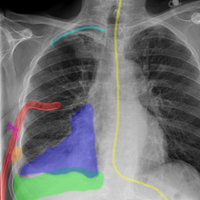

RealWorld Radiology is your ultimate guide to the basics of thoracic imaging. Learn to read chest X-rays in no time and discover the most frequent diagnoses through multiple fully annotated examples.

- Drawings of every radiological finding right on the X-ray

Our cases have been especially selected for their high pedagogical value and real-world representativeness. They can be classified either by diagnosis (e.g. pneumonia, atelectasis, pulmonary fibrosis) or by actual radiological finding (e.g. alveolar opacities, interstitial opacities, silhouette sign), making the learning of the differential diagnosis easier than ever while keeping each case easy to find for quick access.